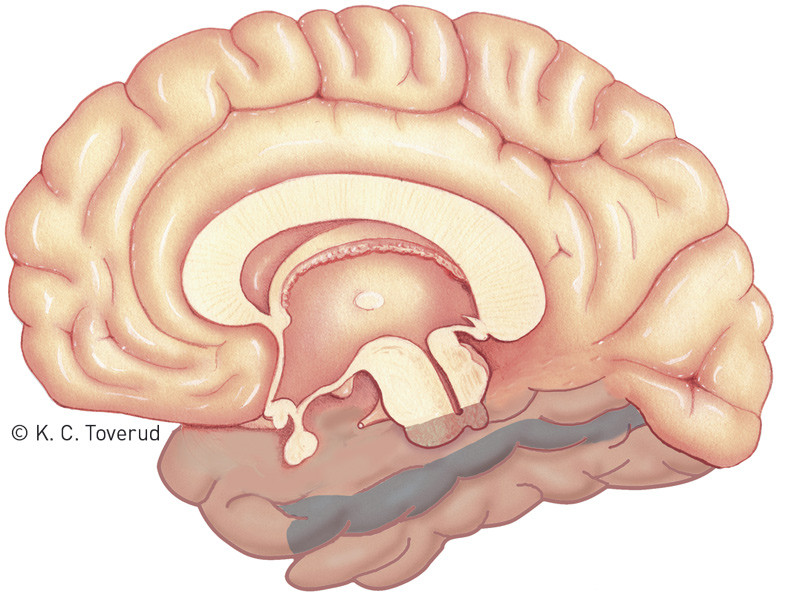

Vår pasient hadde klare kognitive symptomer som pekte mot affeksjon av et spesielt område av hjernen. Det mest slående var at hun ikke klarte å gjenkjenne ansikter og kjenne seg igjen i kjente omgivelser. Utfall i hjernens evne til å tolke visuelle stimuli kan deles inn etter oksipitallappens assosiasjonsfibre til henholdsvis parietallappen («hvor»-utfall) og temporallappen («hva»-utfall) (fig 2) (10, 11). De visuelle agnosiene hører til sistnevnte. De defineres gjerne som manglende evne til å gjenkjenne gjenstander – uten at utfallet skyldes svekket sanseevne eller generell intellektuell reduksjon (altså «hva»-utfall).

Et mindre antall tilfeller som er blitt studert anatomisk og med CT- eller MR-undersøkelse, indikerer at prosopagnosi som oftest er assosiert med bilaterale lesjoner av mediale oksipitotemporale regioner. Det er rapportert unntak som skyldes unilateral skade, nesten alltid på høyre side (14). Hos vår pasient forelå det en trombe i sinus transversus på nettopp høyre side (fig 1). Venøs drenasje fra temporallappen skjer til sinus transversus via vena Labbé (vena anastomotica inferior), og stase i denne venen kan gi sirkulasjonsforstyrrelse i aktuelle hjerneområde. På MR-bildene var det ingen holdepunkter for diffusjonsavvik eller andre parenkymforandringer. Imidlertid lot ikke vena Labbé seg fremstille på aktuelle side, mens det var godt signal i kontralateral vene (fig 3). I sum anser vi at en sammenheng mellom MR-funn og pasientens kognitive symptomer er sannsynlig.

Ut fra humane studier med blant annet funksjonell MR-undersøkelse (fMR) er det sterke holdepunkter for at det finnes et lite område i temporallappens gyrus fusiformis hvor de fleste nevronene er ansiktsspesifikke (fig 4) (15). Oppfatningen at det er et «ansiktsområde» i gyrus fusiformis er en overforenkling, men formidles ukritisk i populærkulturen og dukket i pasientens rekonvalesensperiode opp i James Bond-filmen Spectre. I en scene der Bond er reimet fast i en stol utstyrt med avansert drillutstyr, truer erkeskurken med at han skal drille inn i Bonds gyrus fusiformis og slik ødelegge hans evne til ansiktsgjenkjenning. Utover ytterligere å sementere nevnte overforenkling er det vel nevroanatomisk mer graverende at boret rettes for lavt slik at det sikter mot processus mastoideus og ikke gyrus fusiformis. Bond-skurken er blitt gjenstand for en nevrokirurgisk reprimande i Nature (16).

Vår pasient hadde i tillegg til prosopagnosi problemer med å kjenne seg igjen på kjente steder, såkalt omgivelsesagnosi. Symptomet er nær knyttet til og ofte assosiert med prosopagnosi. Som for prosopagnosi er det oksipitotemporale forbindelser som er rammet, typisk høyresidig, skjønt hos enkelte pasienter er lesjonene bilaterale. Pasienten kan beskrive et sted ut fra hukommelsen eller lokalisere det på et kart, men kjenner seg ikke igjen og går seg bort. Det er altså problemer med «hva» omgivelsene er, men ikke med «hvor» (17). Vår pasient hadde ingen vansker med intellektuelt å forstå at hun var i samme bygning som hun hadde kontor, men hun kjente seg ikke igjen.